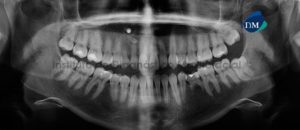

Paciente femenino de 27 años de sexo femenino acude al Instituto de Diagnóstico Maxilofacial para evaluación preoperatoria de cirugía ortognática. A la evaluación de la